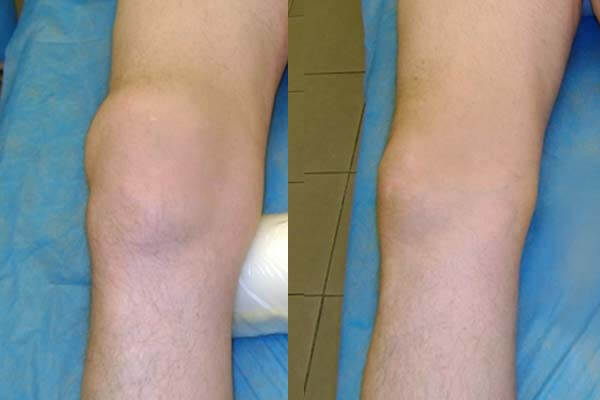

Hasil pengobatan sendi lutut